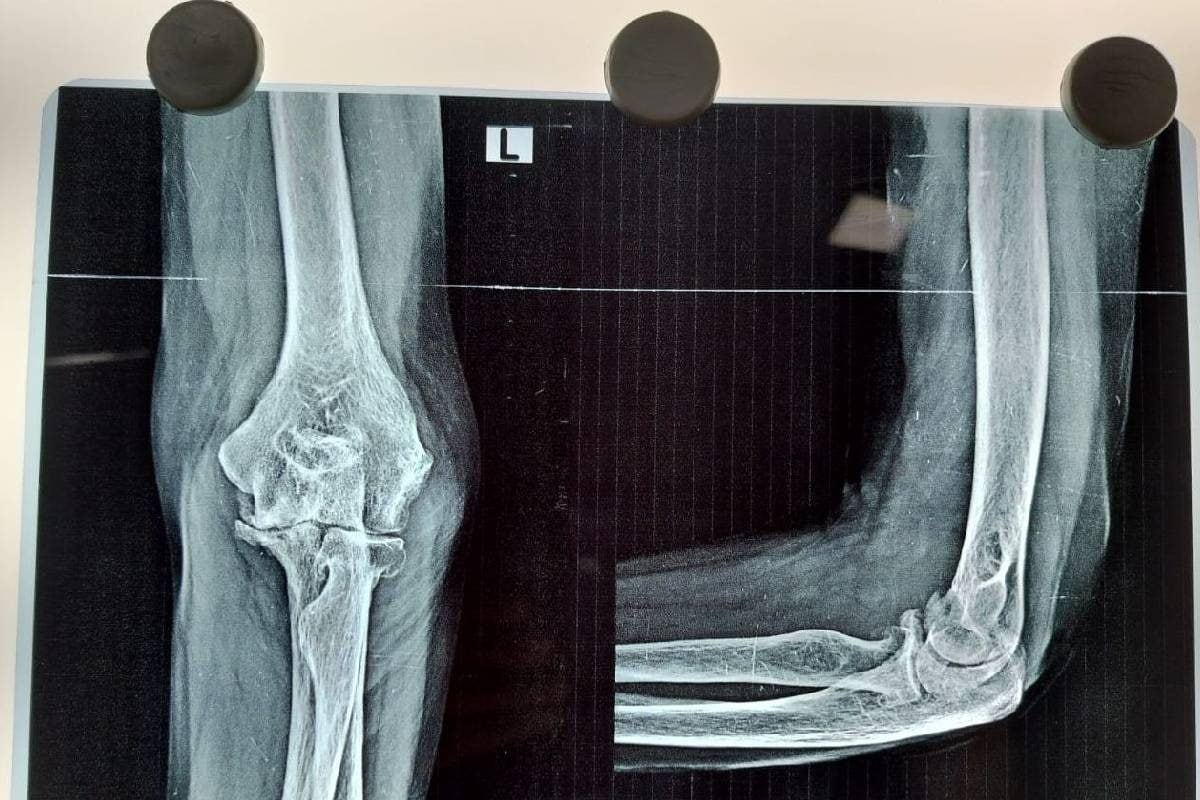

68 साल की मुन्नी देवी का एक हाथ न ठीक से काम करता था और न ही पूरा सीधा होता था. उनकी बाईं कोहनी में एडवांस्ड आर्थराइटिस बीमारी का पता चला था हालांकि गुरुग्राम के सिल्वर स्ट्रीक हॉस्पिटल में टोटल एल्बो रिप्लेसमेंट से अब हाथ लगभग नॉर्मल हो गया है. आइए जानते हैं इसके बारे में..